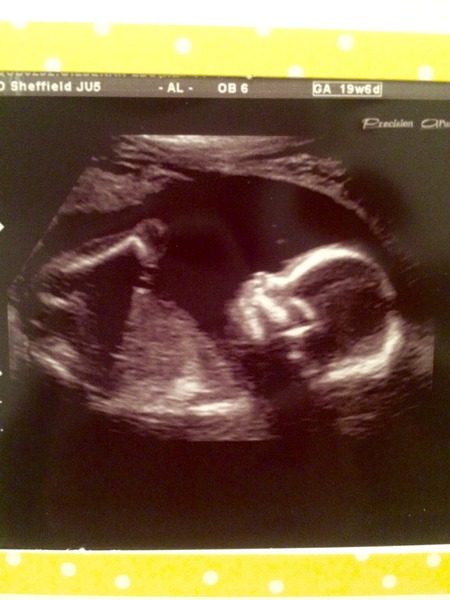

I had my 20 week scan today and all is well. Still team yellow although I'm swaying towards boy now going on the scan picture!

19+6!